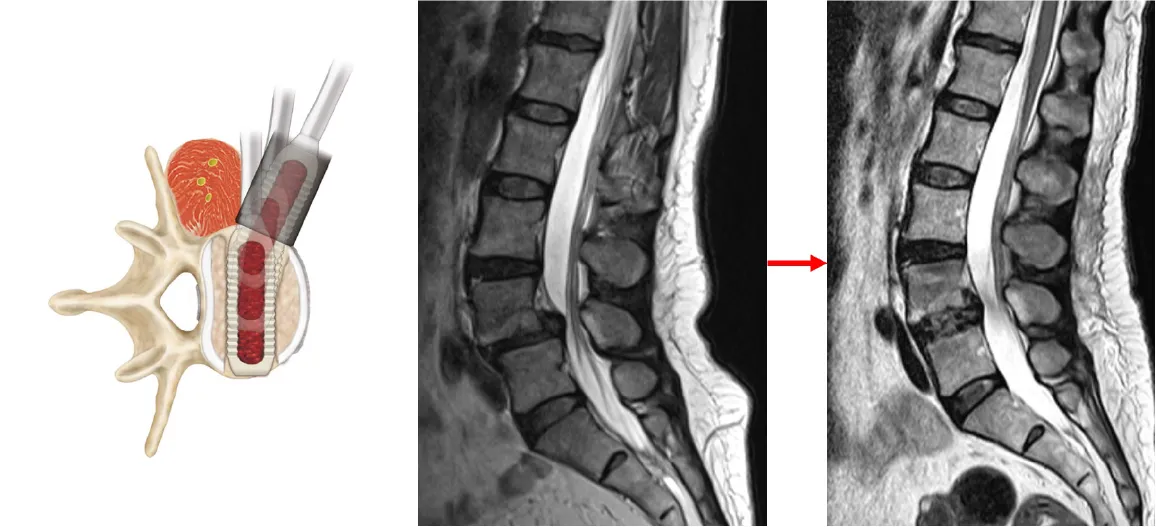

腰椎すべり症

腰椎椎間板の老化に伴い、椎骨が前にズレてくる病気です。中高年の女性に好発します。腰痛・臀部痛・下肢の痛みやしびれなどが出現します。

治療法:症状に応じた保存的な治療が行われますが、効果がなければ手術治療を行います。不安定性が強く背骨の配列に異常を生じている場合などには脊椎固定術が行われます。当院では低侵襲腰椎側方固定術を積極的に行なっています。手術翌日から歩行が可能となり、入院期間は1〜2週間程度です。

腰椎すべり症に対する低侵襲腰椎側方固定術

-

間接的な神経除圧とすべりの整復